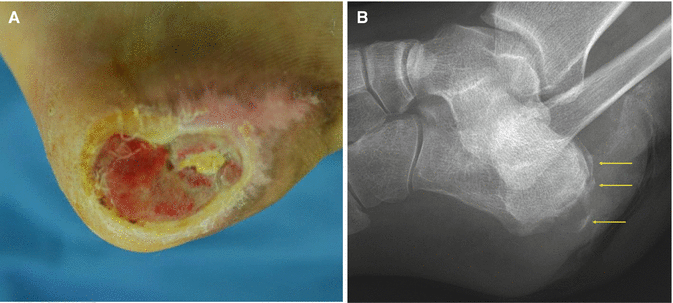

Fig. 7.14

Gross and plain X-ray findings of osteomyelitis (arrows)